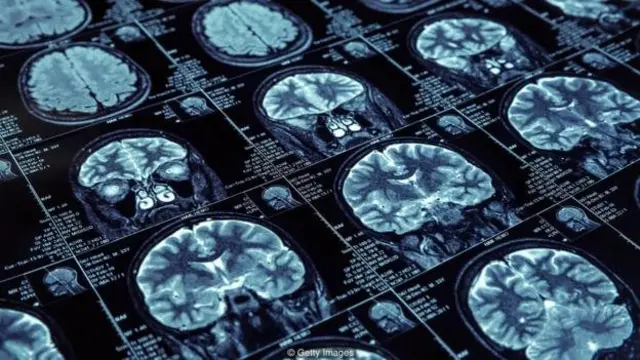

وہاں موجود بستر کے اوپر ایک چھوٹی سی ای ای جی مشین لگی ہوئی تھی۔ جس کامقصد مریض کے دماغ میں ہونے والے عوامل کا باریک بینی سے جائزہ لینا ہے۔ اس کے لیے وہاں ان کے سروں پر الیکٹروڈز موجود ہوتے ہیں۔ یہ دماغ کے سامنے والا، سائڈ والا اور اندرونی حصہ مانیٹر کرتا ہے بلکہ مسلز کی نقل و حرکت اور آنکھوں کے ہلنے تک کو ریکارڈ کرتا ہے۔

تمینن کی حالیہ تحقیق میں سلو ویو سلیپ پر بات کی گئی ہے جسے عرف عام میں گہری نیند کہتے ہیں۔ یہ یاداشت بنانے اور اسے محفوظ رکھنے میں اہم کردار ادا کرتی ہے چاہے وہ گرامر سے متعلق ہو، الفاظ کے ذخیرے سے یا کوئی اور معلومات ہوں۔ یہاں دماغ کے مختلف حصوں کا آپس میں رابطہ بہت اہم ہے۔

گہری نیند کے دوران ہوتا یہ ہے کہ ہمارے دماغ کا جو حصہ ہیپیکمپوس کہلاتا ہے وہ شاید ابتدائی طور پر اس دن سیکھنے والے الفاظ کو ان کوڈ کرتے ہیں۔ ایسے میں دماغ کے مختلف حصوں کا آپس میں رابطہ بہت اہم ہوتا ہے۔

گہری نیند کے دوران ہیپی کیمپس جو کہ جلد سیکھنے کی صلاحیت رکھتا ہے وہ نیو کورٹیکس سے رابطہ کرتا ہے اور اسے لمبے عرصے کے لیے معلومات کو یاد رکھنے کے لیے مستحکم کرتا ہے۔